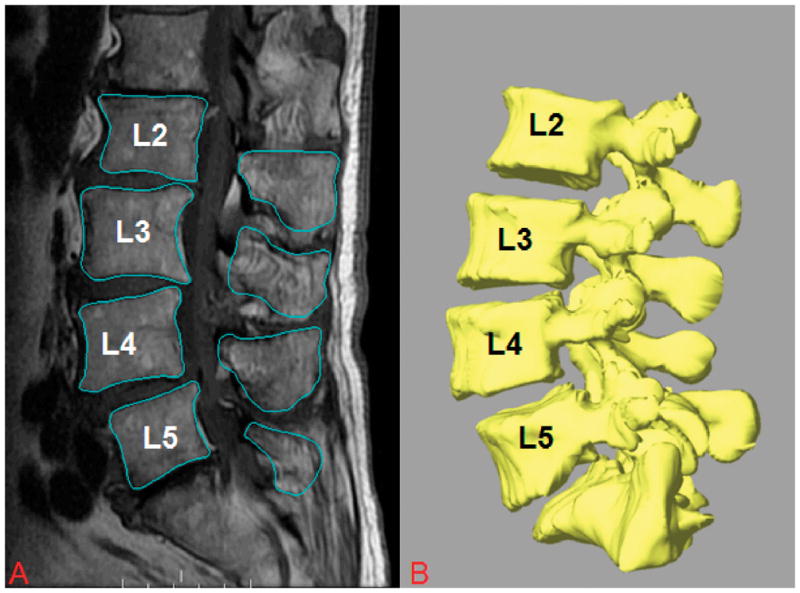

Each patient was scanned using a 3-T MRI scanner (Siemens Medical Solutions MAGNETOM Trio) with a spine surface coil and a T2-weighted fat-suppressed 3-D spoiled gradient recalled sequence. The MR images of the spinal segments were then imported into a solid modeling software (Rhinoceros® Robert McNeel & Associates, Seattle, Washington) to construct 3-D anatomical vertebral models of L2-L5 using a protocol established in our laboratory19, 25(Figure 1A). Mesh models of the vertebrae were created from bony contours (Figure 1B).

Fig. 1.

A, Digitized contours of lumbar vertebrae of patients with DLS at L4–L5 in the sagittal plane. B, Three-dimensional anatomical vertebral model of L2–L5, constructed from the magnetic resonance imaging.